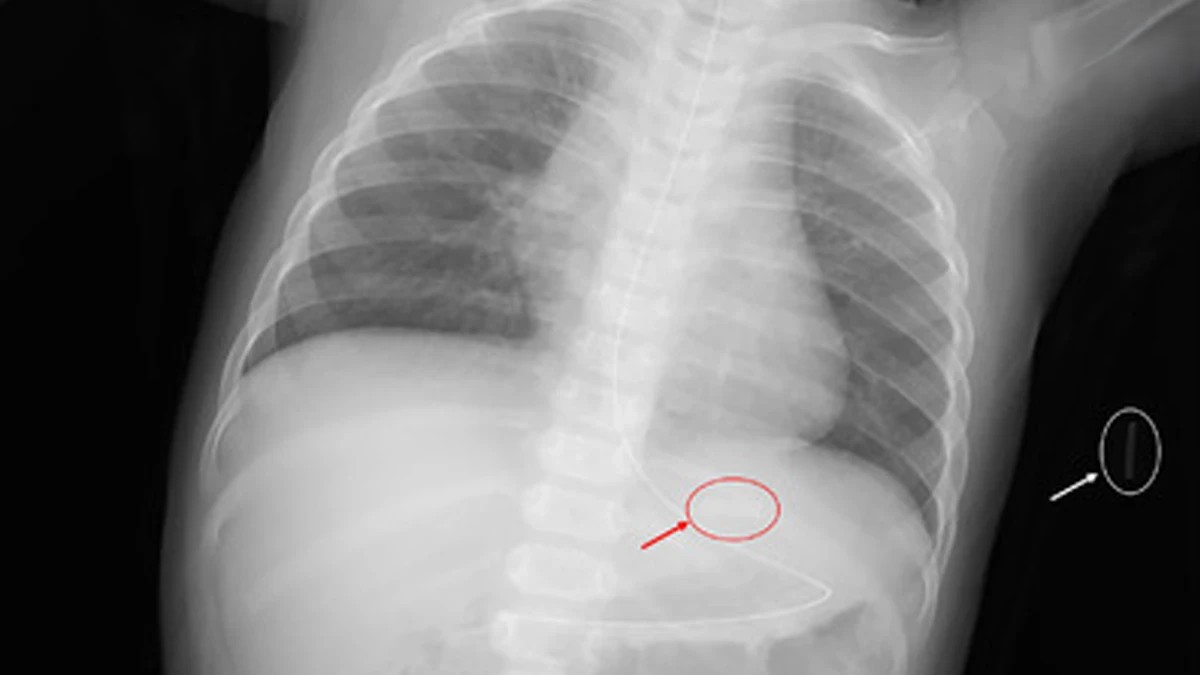

危機暗藏 國際加熱菸傷童案例頻傳 台灣審查機制亟待完善

健康中心/綜合報導 加熱菸審查結果即將出爐,未來可能在台灣「合法上市」,然而國際間已傳出多起兒童誤食加熱菸菸彈